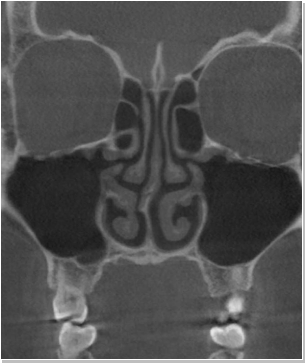

비염

비중격만곡증

축농증